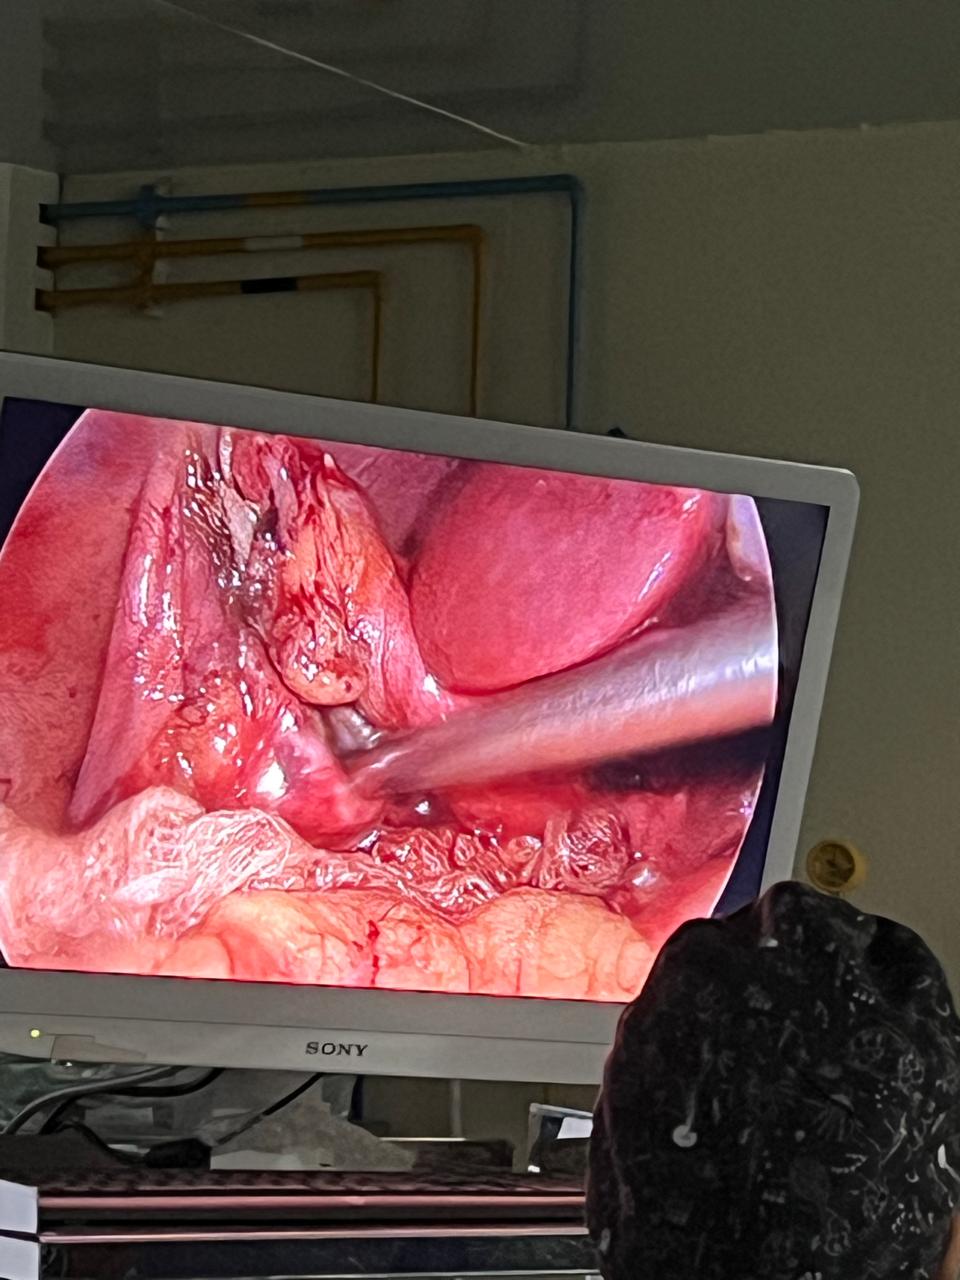

Welcome to our gallery, where you can explore a visual journey of our state-of-the-art surgical facilities, advanced medical equipment, and the exceptional care provided by our dedicated team. Here, you’ll find images showcasing our modern operating rooms, comfortable recovery areas, and the skilled professionals who ensure the highest standards of patient care.

Our gallery also features before-and-after photos of successful procedures, highlighting our commitment to transformative, evidence-based surgical practices. We invite you to browse through and witness the excellence and compassion that define our surgical practice.